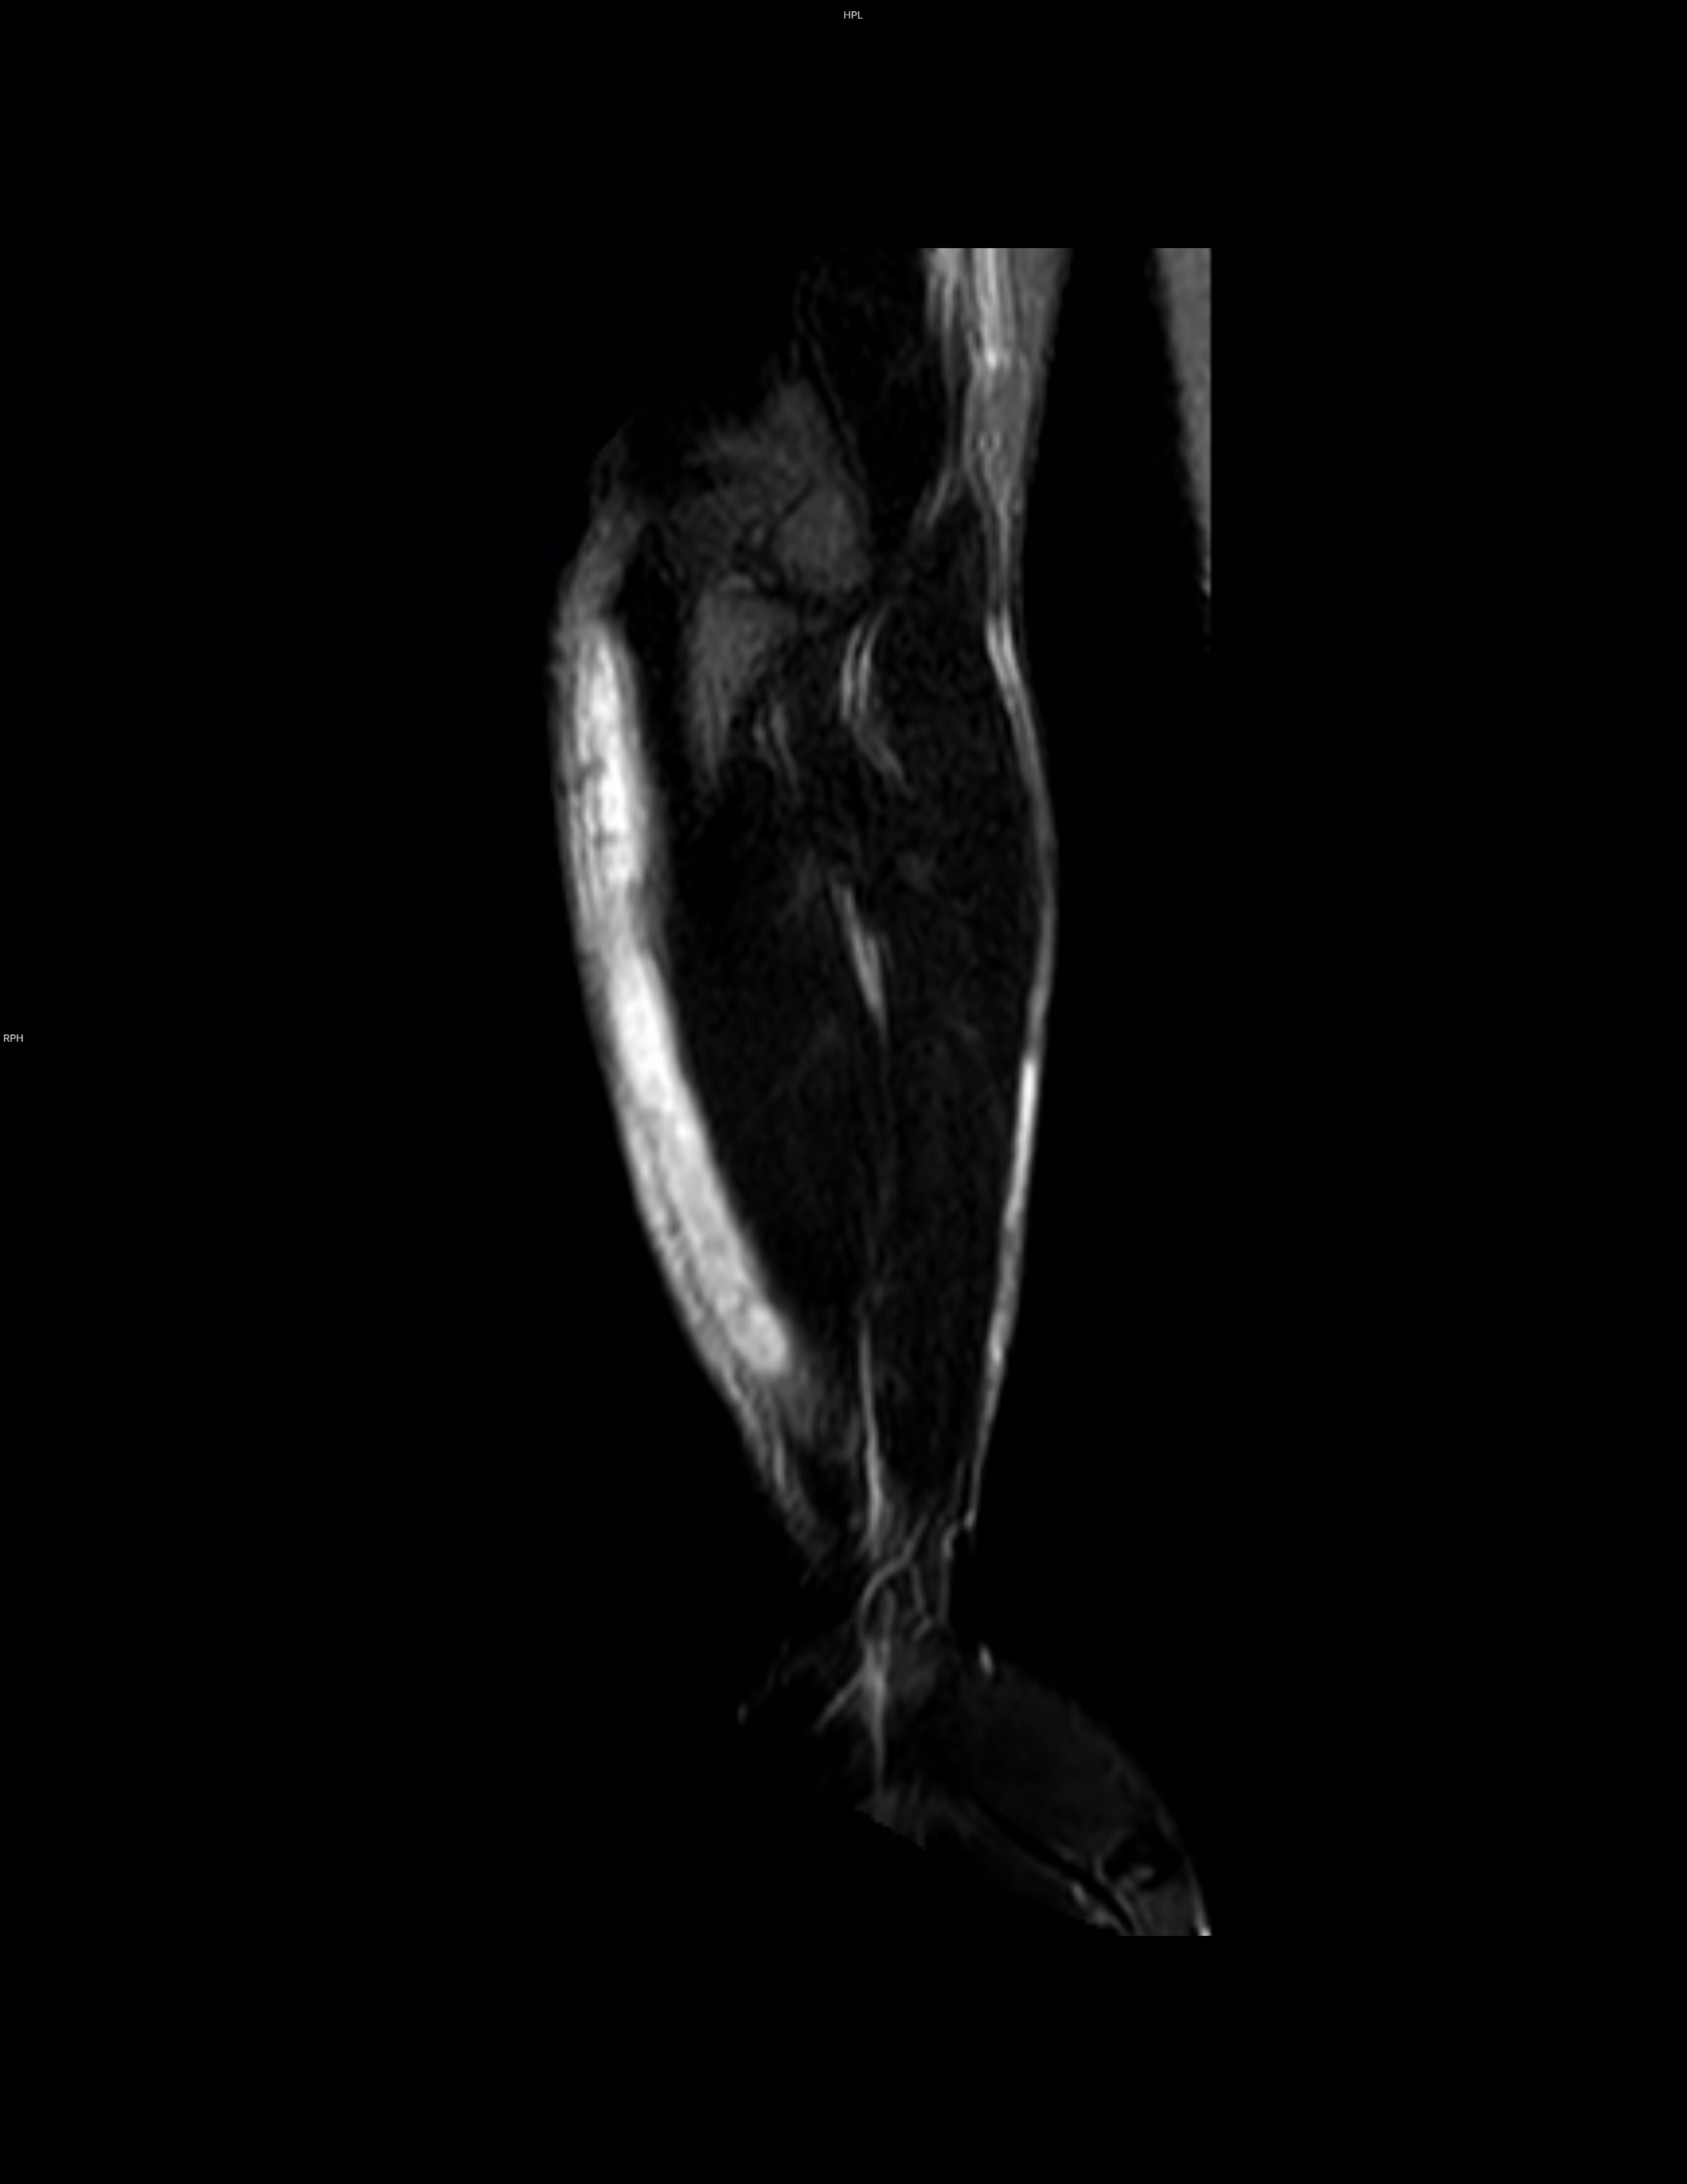

antebrazo existe una colección superficial a la musculatura que tiene intensidad de señal heterogénea octubre 27, 2025 drfroy Deja una respuesta Cancelar la respuestaTu dirección de correo electrónico no será publicada. Los campos obligatorios están marcados con *Comentario * Nombre * Correo electrónico * Web Δ Este sitio usa Akismet para reducir el spam. Aprende cómo se procesan los datos de tus comentarios. Buscar Search for: Search Acceso Acceder Feed de entradas Feed de comentarios WordPress.org Amigos Casos clínicos enarm Como bajar de peso Oscar Blancarte panchosoft Vitalis Sigueme.